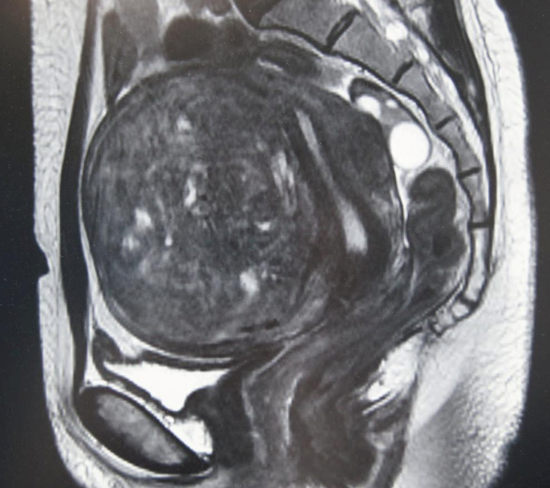

婦人科では、子宮筋腫、卵巣腫瘍、子宮内膜症などの良性疾患、子宮がんなどの婦人科悪性腫瘍の手術・治療を、他診療科と連携し横断的に行います。